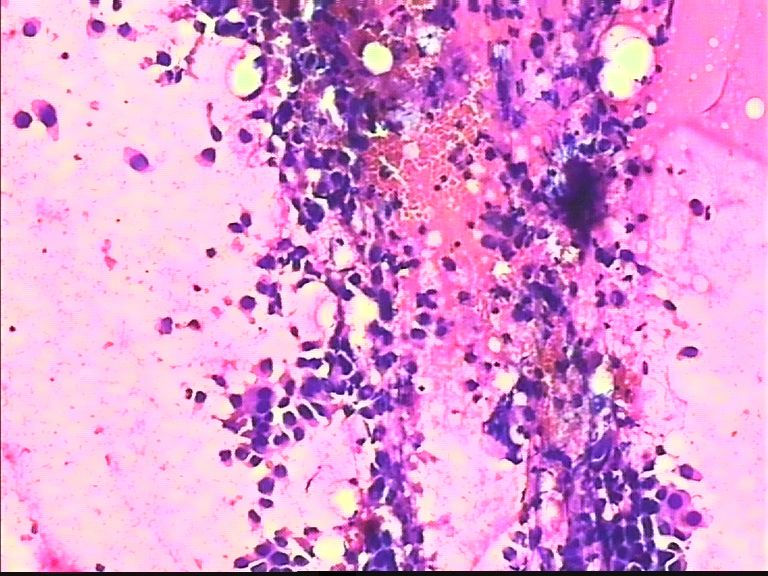

38岁 乳腺肿瘤 女

考虑癌:图18细胞核形式不规则,染色质粗块状,可见核仁.

从所给图看恶性是没什么问题!染色有点过,染色质结构欠清晰;关于细胞学判断浸润的问题我想应综合来判断,如单个细胞的异形性,细胞整体弥散情况,细胞微粒结构以及间质成分等等,个人的认识也起到一定因素,细针穿刺中最常规用的还是--导管癌。

浸润导管癌